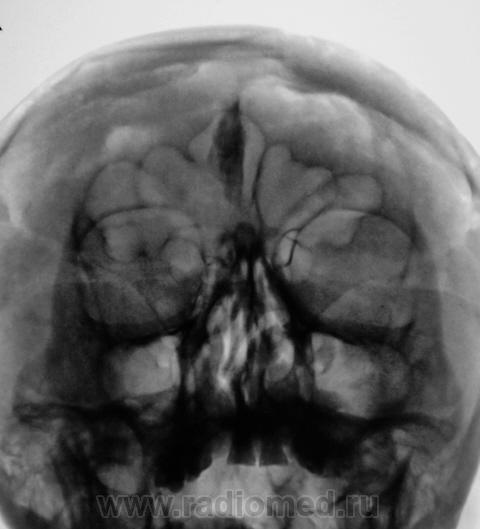

Пациент направлен на рентгенографию ППН по причине предстоящей операции «на глазах».

Обызвествилась не нужная часть мозга

Обызвествление серповидного отростка.

А, меня, что-то смутила чешуя лобной кости...

Действительно, лобная кость какая-то "кучерявая", а в боковой проекции не доснимали?

Прямая проекция.

Вены широковаты и боковые лакуны также выражены. Возможно на фоне остеопороза. Возраст, вероятно, немолодой.

Гиперпневматизация лобных пазух. Обызвествление серповидного отростка. Вероятно, повышение внутричерепного давления (сосудистый рисунок). Искривление носовой перегородки вправоsmiley. На нижнюю треть верхнечелюстных пазух "наслоились" пирамиды височных костей.